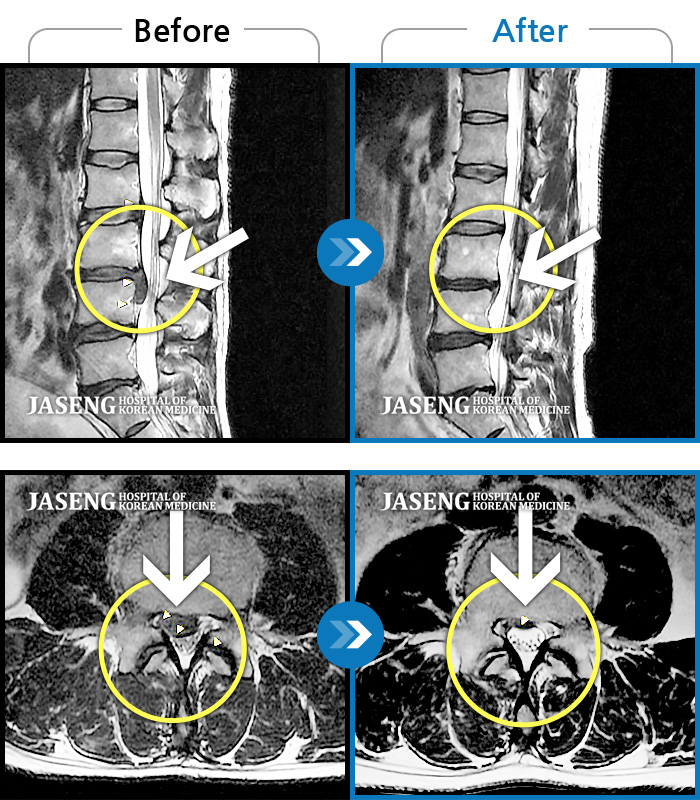

허리디스크

해운대 · 이상건 원장

허리디스크로 인한 요통

촬영시기

2018.04.21 ~ 2018.11.10